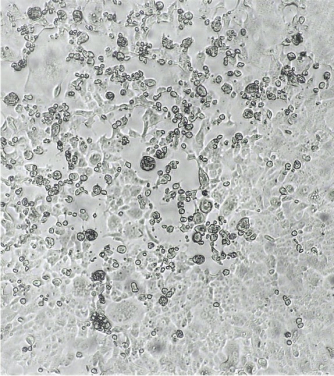

To test the ability of vaccine recipients' serum antibodies to neutralize the Omicron variant, the team used sera from two groups of vaccine recipients who have received two doses of BNT162b2 (BioNtech) or Coronavac. Each group consists of 25 people.

Two Omicron variants present in Hong Kong were tested, one from South Africa and the other from Nigeria (with the additional R346K mutation). The ability of serum antibodies to neutralize the Alpha, Beta, and Delta strains was also tested as a control.

Only five out of 25 Biontech vaccine recipients had neutralizing ability against the Omicron variant virus, and the vaccine efficiency was significantly reduced to 20 - 24%. Compared to the original SARS-CoV-2 strain, the titer of neutralizing antibodies against the Omicron variant has decreased by 36 - 40 fold.

None of the serum of the 25 Coronavac vaccine recipients contain sufficient antibody to neutralize the Omicron variant at the limit of 1 in 10 dilution.